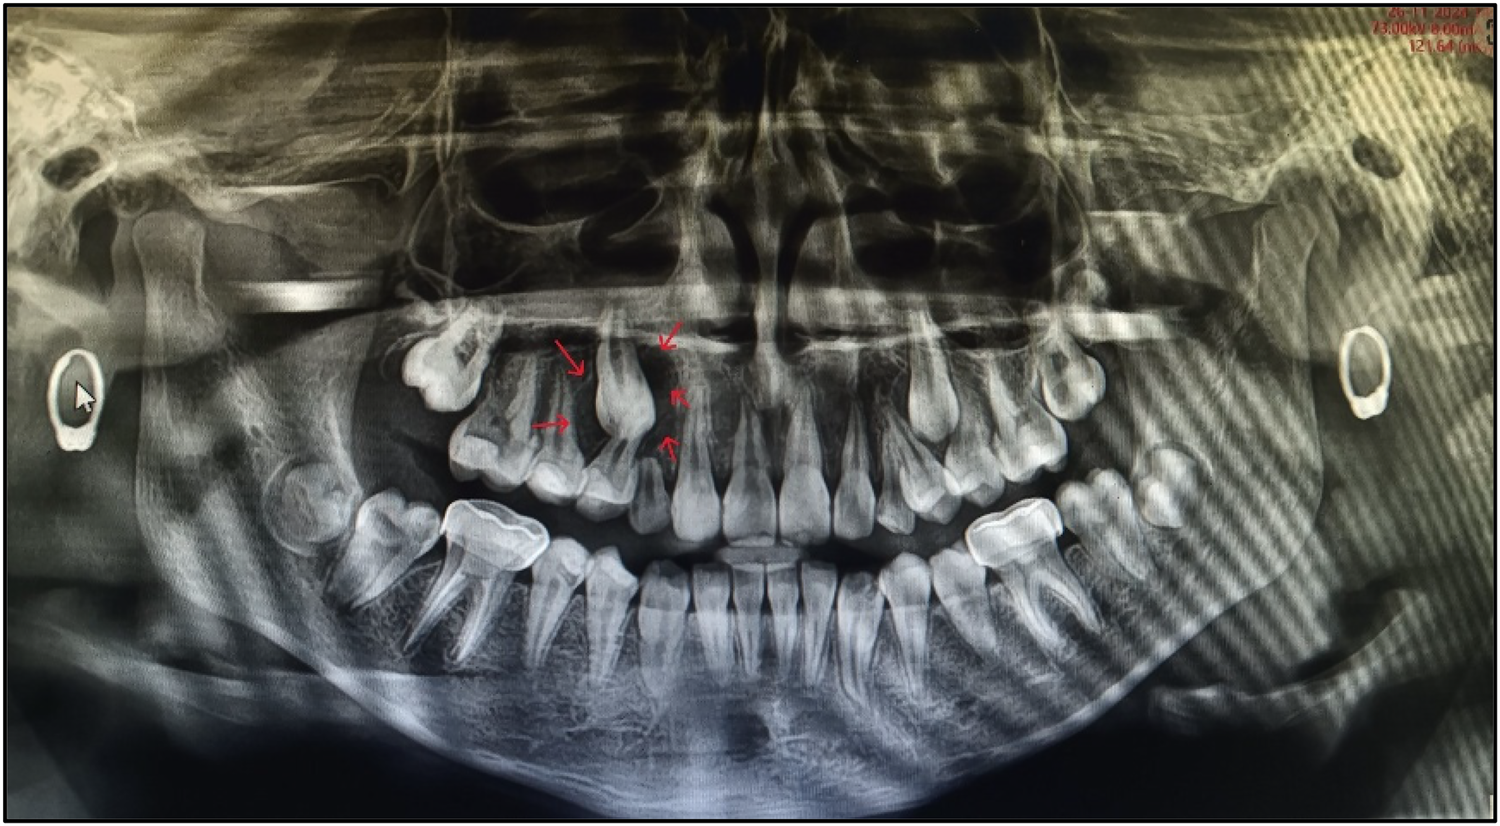

An OPG was taken (Figure 2). On the basis of radiographic examination, we arrived at the following diagnoses (Table 1):

• Teeth 14, 15, 27, 33, 37, 44, 45, and 47: pre-eruptive intracoronal resorption.

Nolla staging was performed for the teeth affected by PEIR (Table 2).